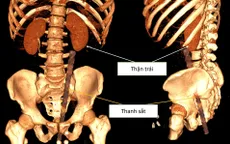

VTV.vn - Bé gái 13 tuổi ở Lâm Đồng phải phẫu thuật cấp cứu do nhiều mảnh xương gà mắc trong ruột non, một dị vật đâm thủng ruột gây viêm phúc mạc, đe dọa tính mạng.